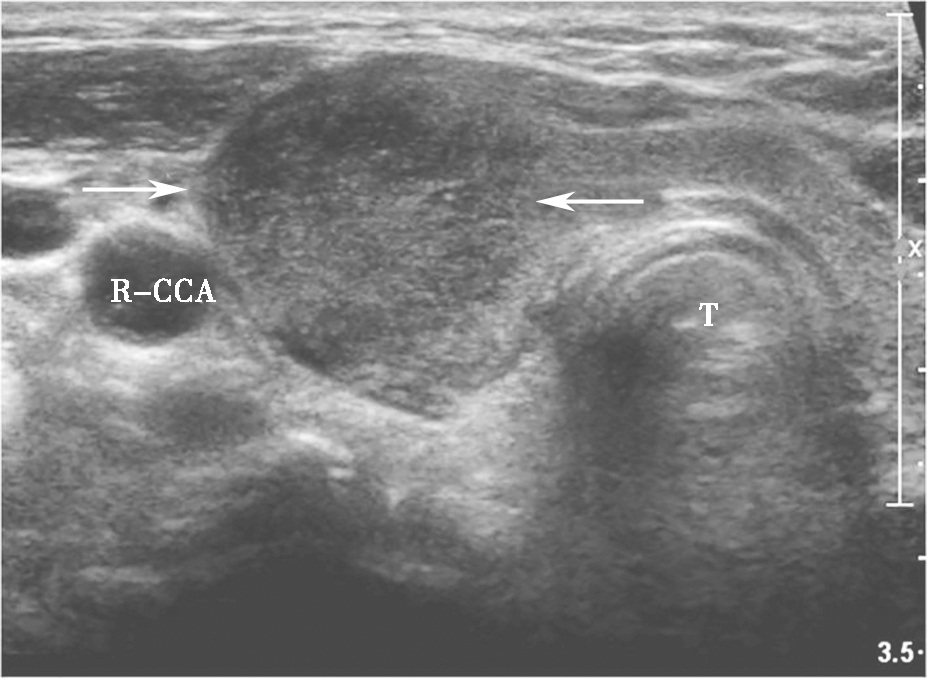

甲状腺髓样癌超声上多为不规则低回声实性结节,内部回声不均,部分病例可伴有囊性成分,髓样癌丰富的血流信号是其超声主要特点。约1/3的髓样癌超声表现不典型,除了血供丰富表现外,类似良性结节(图13、图14)。

,分叶状,可见囊性成分及点状强回声(微小钙化).jpg)

图13左侧颈部纵切面:甲状腺左叶中部中低回声(箭头所示),分叶状,可见囊性成分及点状强回声(微小钙化)